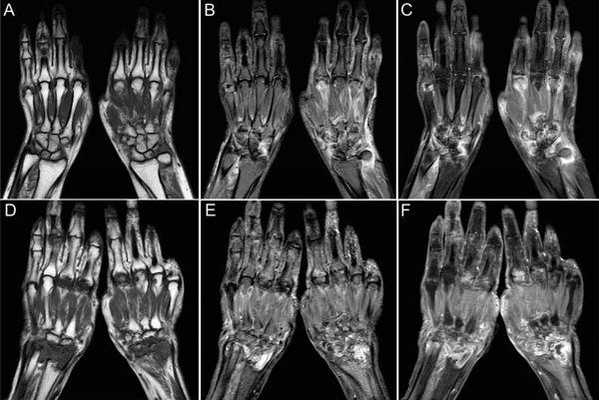

МРТ кисти

МРТ кисти, как и МРТ других суставов, применяется для выявления различных повреждений, прежде всего связочного аппарата, костных переломов (в дополнение к рентгенографии) и оценки состояния суставов. В лучезапястном суставе оценивается конгруэнтность и наличие жидкости.

На рентгенограммах хорошо видны дистальные переломы лучевой кости. Проблема диагностики возникает когда нет костных повреждений, но есть нестабильность. Ее можно определить на рентгенограммах по косвенным признакам - нарушению характерной линии вдоль соединения костей и увеличению расстояния между некоторыми из них. Однако только МРТ дает возможность увидеть разрывы связок, приводящие к нарушению конфигурации в запястье.

Из связок при МРТ кисти, прежде всего, оценке подлежит ладьевидно-полулунная, полулунно-трехгранная и треугольный фиброзно-хрящевой комплекс. Дополнительное значение имеют внутренние связки запястья, которые сложным образом соединяют мелкие кости между собой, а также с лучевой костью. Толщина этих связок от 1 до 3 мм. Повреждение перечисленных связок, особенно, полное или частичное заднего компонента, приводит к нестабильности в суставе. Фиброзно-хрящевой комплекс состоит из треугольного фиброзно-хрящевого диска и нескольких коротких связок, соединяющих кости запястья между собой, а также проксимальные концы локтевой и лучевой костей.

МРТ кисти. Корональная Т1-взвешенная МРТ. Нормальное изображение ладьевидно-полулунной связки. Обозначения: S - ладьевидная кость (scaphoid), L - полулунная кость (lunatum), T- трехгранная кость (triquetrum).

МРТ кисти. Корональная градиентная МРТ. Нормальное изображение полулунно-трехгранной связки. Обозначения: S - ладьевидная кость (scaphoid), L - полулунная кость (lunatum), T- трехгранная кость (triquetrum).

МРТ кисти. Корональная Т1-взвешенная томограмма с подавлением сигнала от жира. Ладьевидно-трапецевидная связка в норме. Обозначения: S- ладьевидная кость, Td - трапециевидная кость, Tm - трапеция.